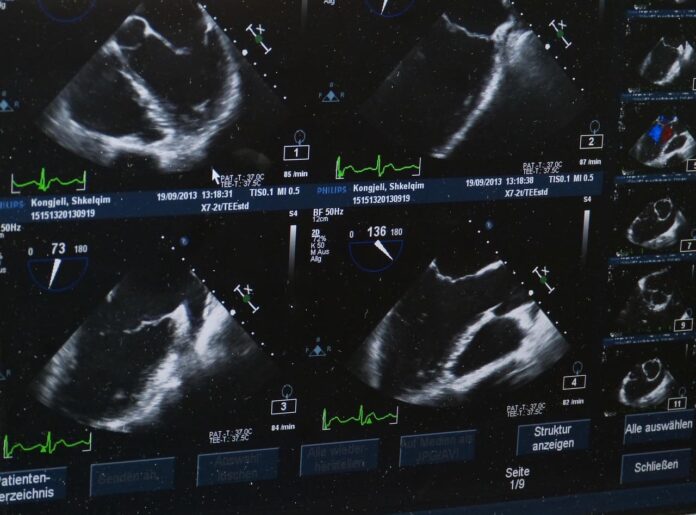

La force de l’échographe réside dans sa capacité à fournir, en temps réel, une image fidèle de l’appareil génital féminin. Lorsqu’un kyste ovarien est suspecté, l’état de la muqueuse utérine interrogé, ou la viabilité fœtale évaluée, rien ne remplace la vision directe offerte par la sonde endovaginale ou transabdominale. Cette précision immédiate :

- Technologie avancée : modes Doppler haute sensibilité, imagerie 3D/4D pour des coupes volumétriques, algorithmes d’optimisation automatique de l’image.

- Outils d’intelligence artificielle embarqués, capables de repérer automatiquement des zones d’intérêt (notamment dans le dépistage des masses pelviennes).